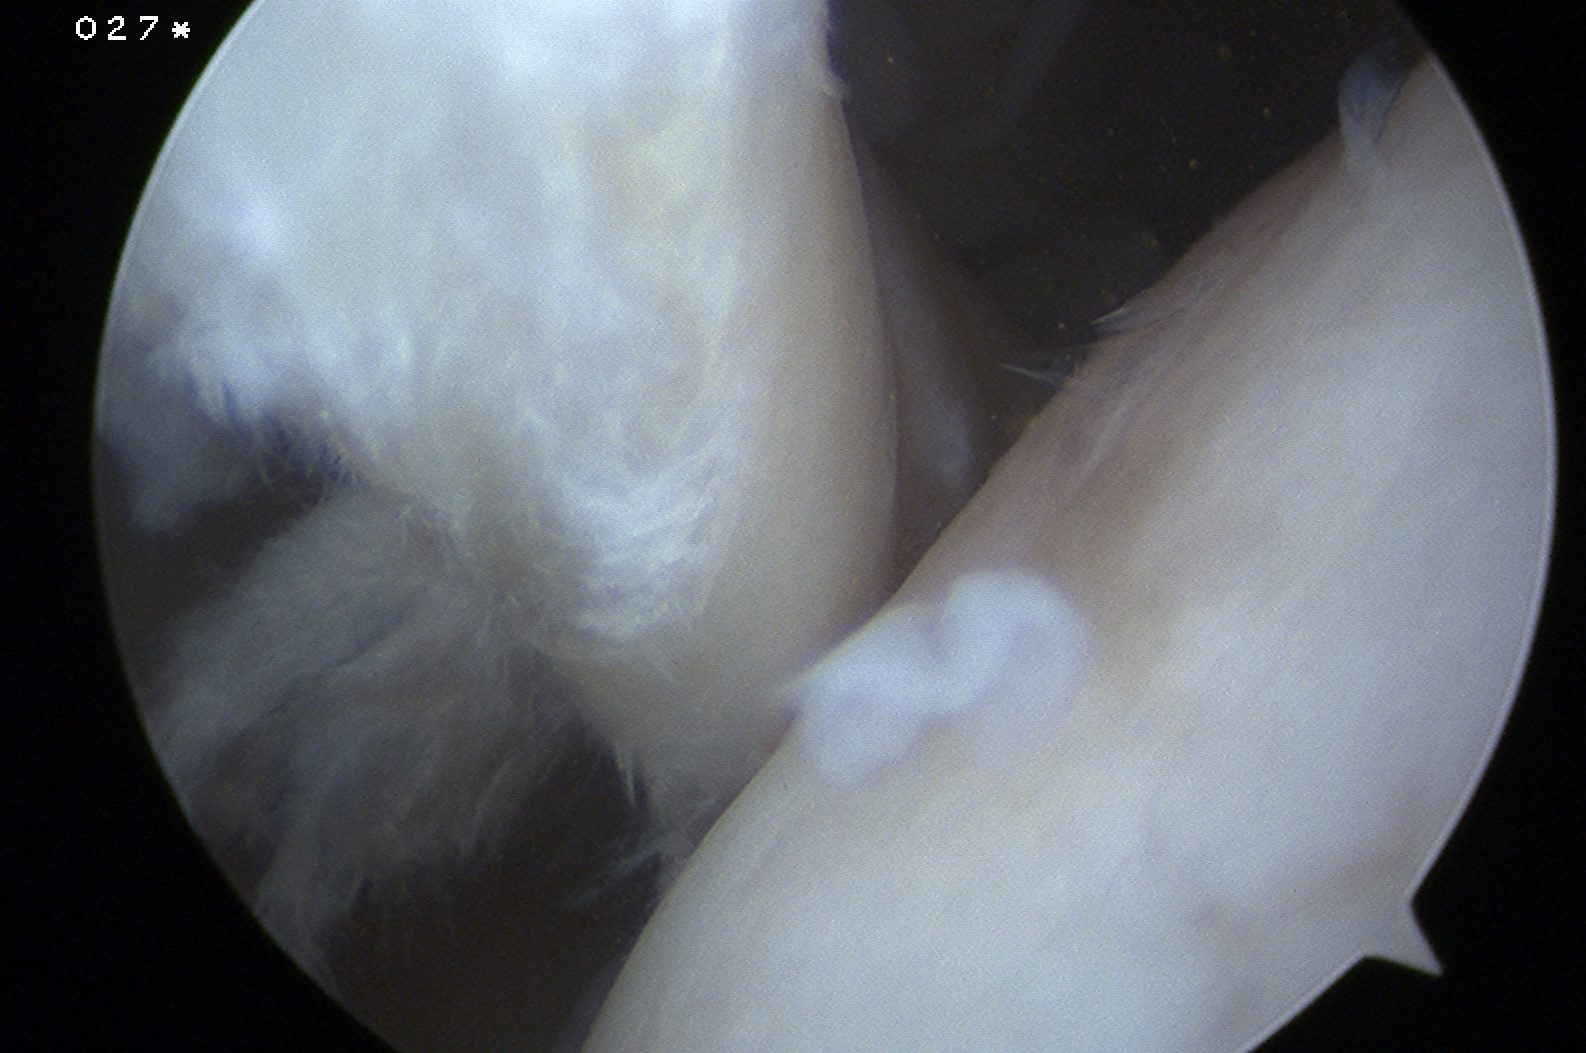

Tendonopathy

Medial subluxation of LHB